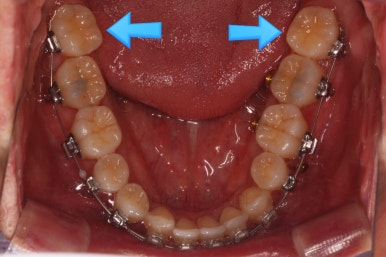

이 뽑은 자리로 앞니를 쭈욱 밀어넣으며 비대칭도 맞춰주기 위해서 미니스크류(마이크로 임플란트)라고 불리는 작은 나사를 잇몸뼈에 식립했어요.

이를 지지대로 삼아서 치아를 움직이게 됩니다.

아랫니를 계속 당겨주면서 가지런하게 하고 있어요.

화살표는 사랑니인데요. 이 분의 경우 아래 앞니가 1개 없고, 1개를 추가로 뽑아서 윗니 대비 아랫니가 총 2개 모자란거죠.

운이 좋게도 이 분은 사랑니까지 잘 나와있던 상태라 내버려두기 아까워 함께 가지런하게 해주고 사용하실 수 있게 해드렸어요.